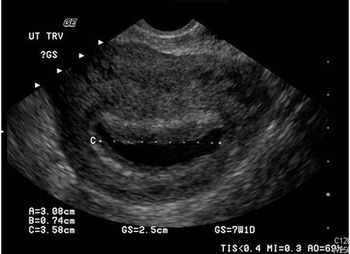

The pain and bleeding have persisted for 2 days. She last menstruated 5 weeks ago but doubts she is pregnant. Take a close look at the ultrasound image. Your Dx?

Results of a pelvic sonogram reveal the etiology of lower abdominal pain and vaginal bleeding in a 26-year-old woman.